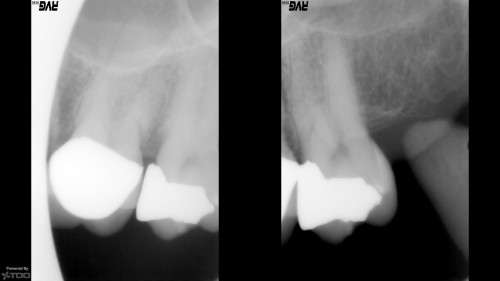

Core Only

65 year-old female in good health.  Root canal treatment was completed by my predecessor 15 […]